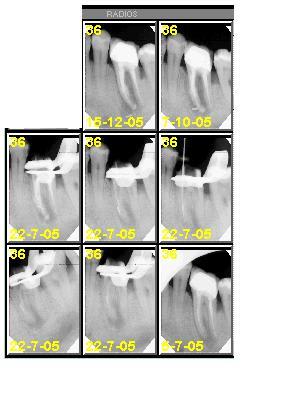

aucun système n'est parfait mais pr etre passée de l'un à l'autre depuis 3ans et reprendre des RX sytematiques(curiosité intellectuelle) je préfère mes endo mécanisées...